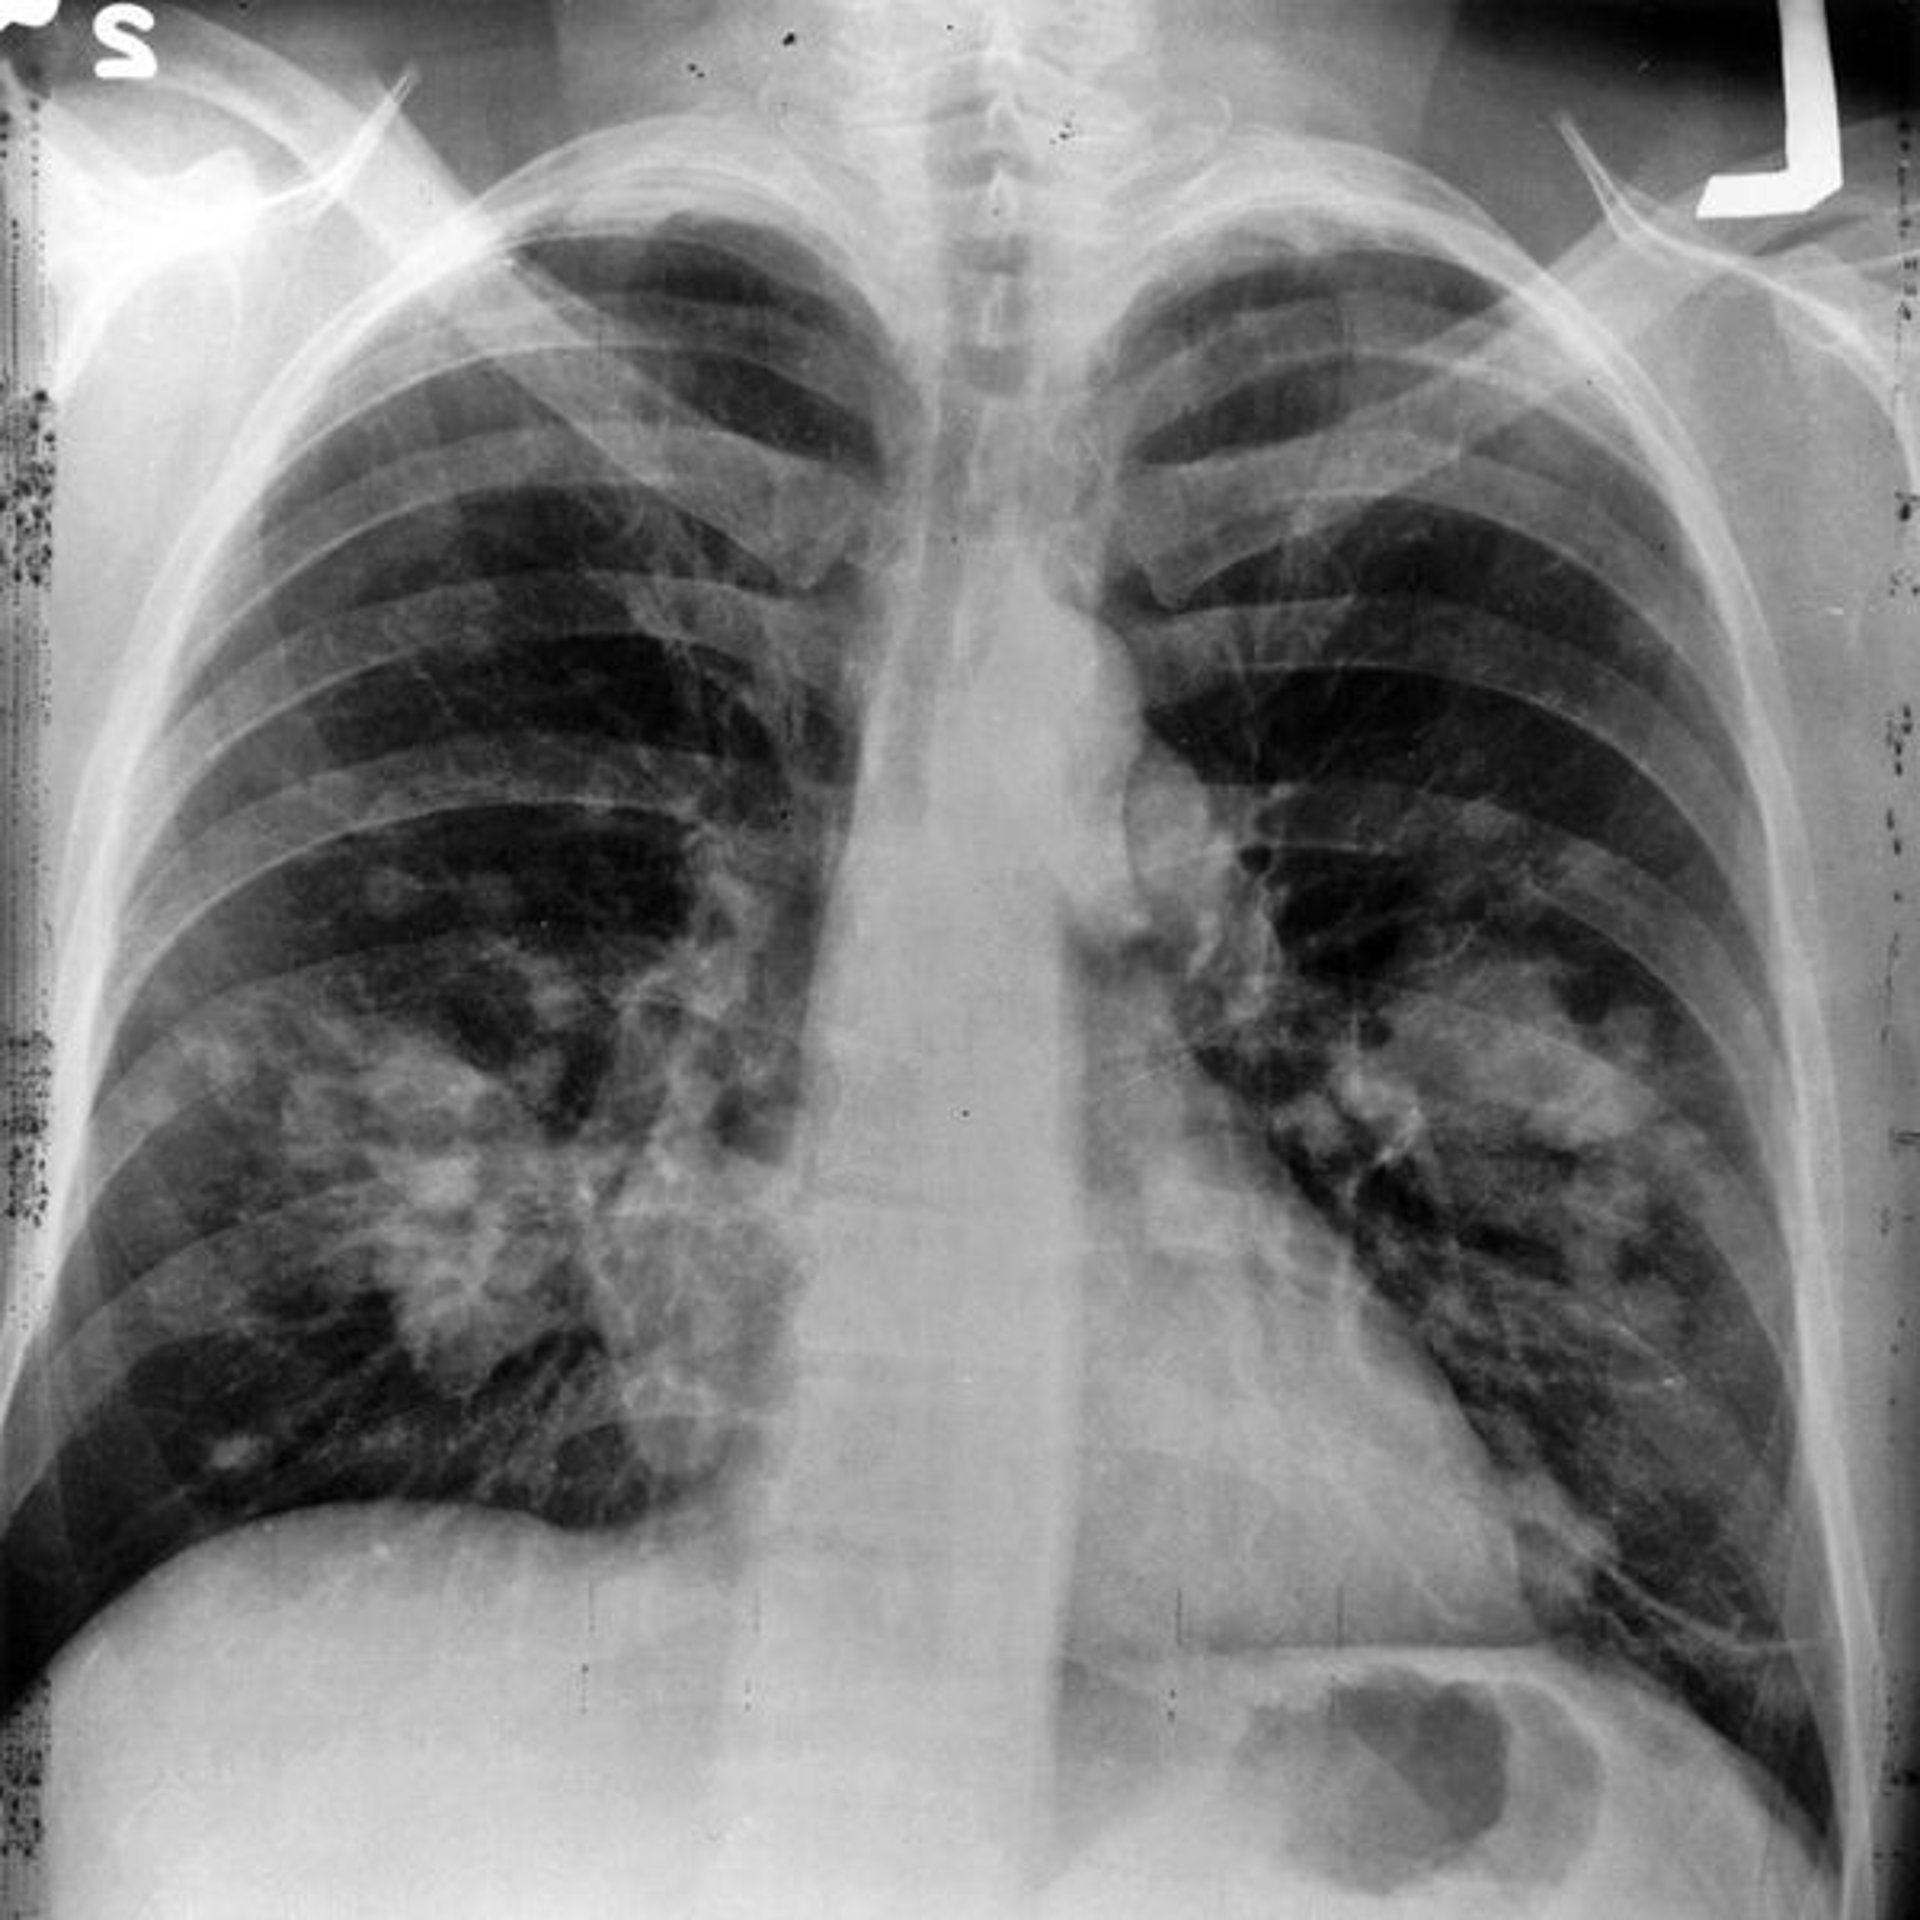

Dos mutaciones genéticas elevan el riesgo de cáncer de pulmón

Cáncer De Pulmón

NATIONAL CANCER INSTITUTE/WIKIMEDIA COMMONS